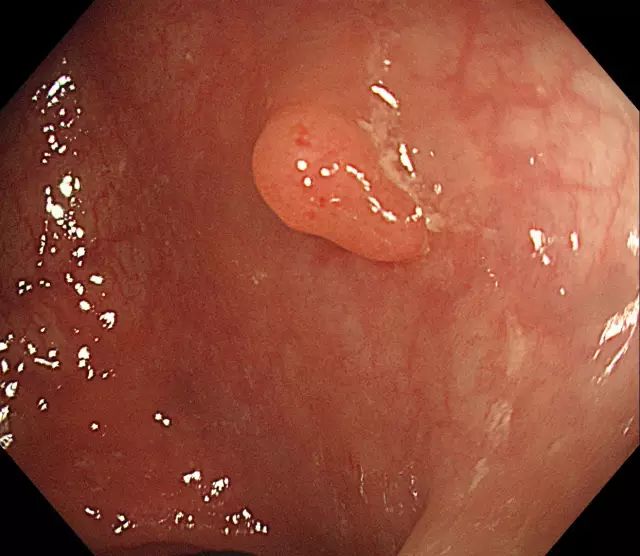

步骤一:发现息肉,并将其暴露于视野正中。

图片